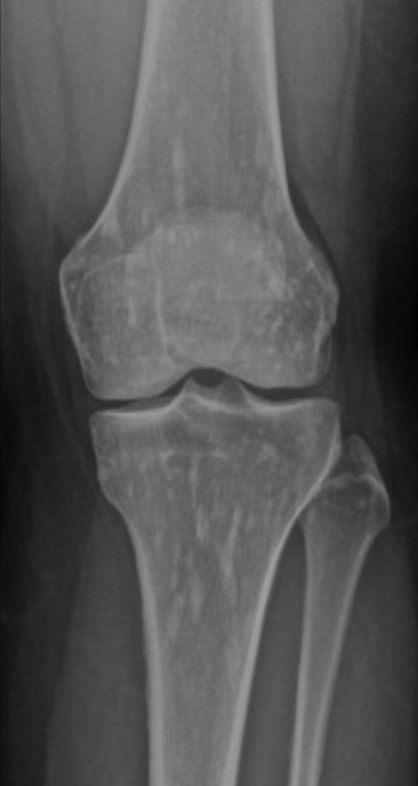

Giant Cell Tumor

• Age 30-60

• Criteria

• Physis must be closed

• Non-sclerotic border

• Abuts articular surface

• 60% at knee

• Eccentrically located (not central)

• Typically metaphysis

• Lytic lesion on radiograph

• Quasi-malignant - have pulmonary mets

• Look for epiphyseal mass + lung mass in patient <40!, if >40 then mets